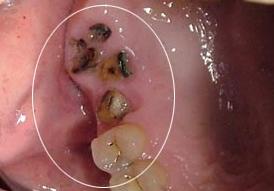

1.由龋所造成的严重的不能保留的残缺牙齿:经常不是很严重的龋齿需要修补或者嵌体修复。对于一些中度严重的龋齿需要做根管治疗并做全冠来修复。然而对于非常严重的龋损就需要及时拔除,做出及时治疗为后期的种牙或者镶牙做准备。